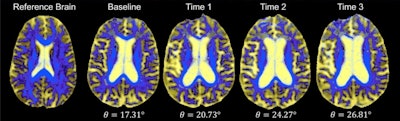

DSEG images for axial brain slices of SVD patients. Images in the SVD brain are shown over three time points with DSEG Θ angle scores for microstructure changes. Increases in Θ show substantial DSEG changes in brain microstructure over time with increasing brain damage. © 2017 The Authors (CC BY-NC-ND 4.0).

The developed methodology utilizes a diffusion tensor image segmentation (DSEG) technique, combining several MRI-detectable SVD markers to produce a sensitive singular score for disease severity and brain damage. This enables monitoring of alterations in brain microstructure over time via a single angular measure -- DSEG Θ.